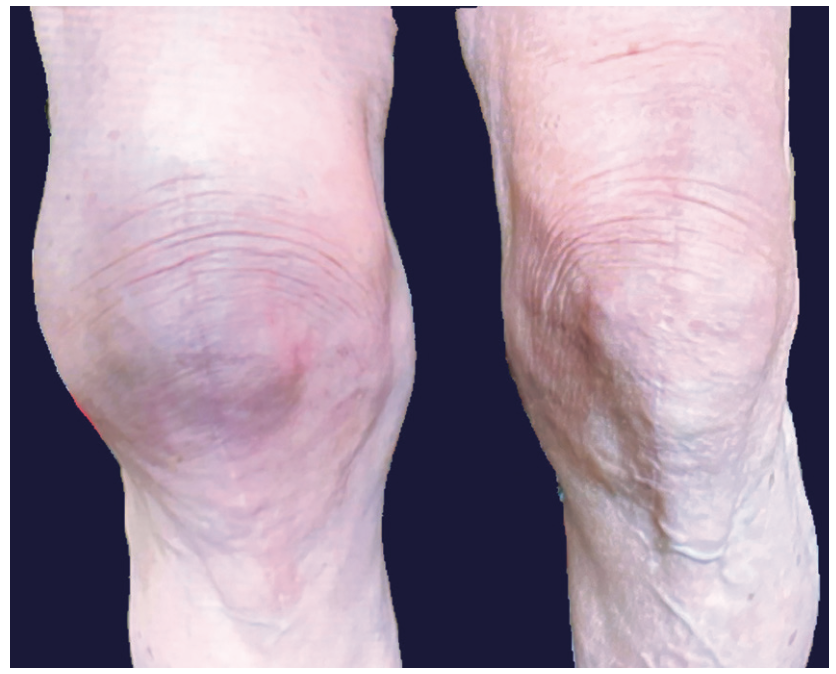

A 68-year-old female presented to our office with recurrent, painful swelling to her right knee following total knee replacement 2 years prior. She reported recurrent swelling and pain shortly following the surgery with no other inciting traumatic event (Figure 1). Multiple joint aspirations showed bloody fluid. Infectious and inflammatory arthritis had been ruled out via joint fluid analysis and serological testing. In addition, testing ruled out bleeding disorders and the patient was not on anticoagulant medications. Further evaluation for implant failure and malalignment was benign. Conservative management was attempted initially, including repeated joint aspiration. When conservative measures failed, interventional angiography with selective embolization was performed for diagnosis and treatment. The patient had lateral-dominant osteoarthritis and a decision was made to target the inferior lateral genicular artery.